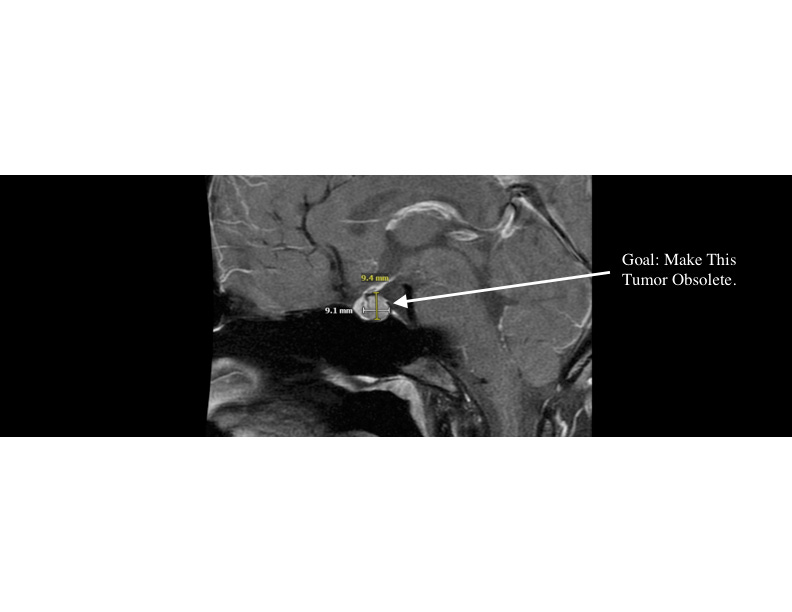

curing my partner's incurable brain tumor | ai for science VC @ Side Door Ventures, prev biophysics research @columbia, ops@pioneer labs, vc @angellist, 2x founder